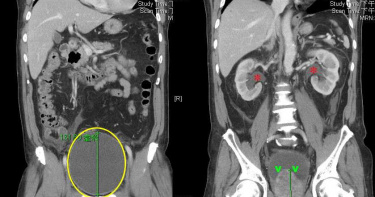

男睪丸腫痛求醫 為難吐病情:用肛門射精、陰莖排糞尿

超罕見病例!一般人對於男性的生殖與泌尿系統的認知,多半是精液從陰莖射出、肛門解出糞便。但美國一名33歲男子,因為睪丸腫痛難耐就醫,害羞又為難的向醫師透露,自己在過去的2年間,精液會從肛門排出,糞便也會透過陰莖中的尿道解出,經過診斷,發現這名男子的尿道與直腸之間,存在瘻管(fistula)或異常的通道,才會導致各種液體和固體,經由此通道錯亂流通。根據《每日星報》引述科學網站《IFL Science》報導,該名男子求診時自述,過去2年間,他會在排尿時,從尿道同時解出糞便,稱為糞尿(fecaluria);而原本該從陰莖射出的精液,竟會改從肛門射出,讓他不堪其擾,但他長期以來羞於就醫;這次會來看診,是因為睪丸腫痛難耐,才來求助醫生。經過檢查,醫師發現男子除了睪丸腫大和尿道感染外;透過電腦斷層掃描看見,男子直腸附近有一個「充滿氣體的結構」(gas-filled structure),再深入檢查後證實,男子的尿道與直腸間存在瘻管(fistula)或異常的通道,導致各種液體和固體,經由此通道,胡亂交錯流通,造成身體的不適。醫師再經過詳細問診發現,男子2年前曾因為濫用古柯鹼與中樞神經迷幻劑PCP(俗稱天使塵),中毒昏迷3周,當時他被插導尿管,可能因此造成受傷,當前的症狀,有可能是住院時插尿管所造成的後遺症。德州加爾維斯頓醫學院分校的內科醫學生Frank L. Ventura表示,此案例可能是安置導尿管時,所引發的罕見併發症,男子的瘻管已逐漸痊癒,透過病例的研究,提醒醫師應注意,尿道損傷等其他潛在風險。